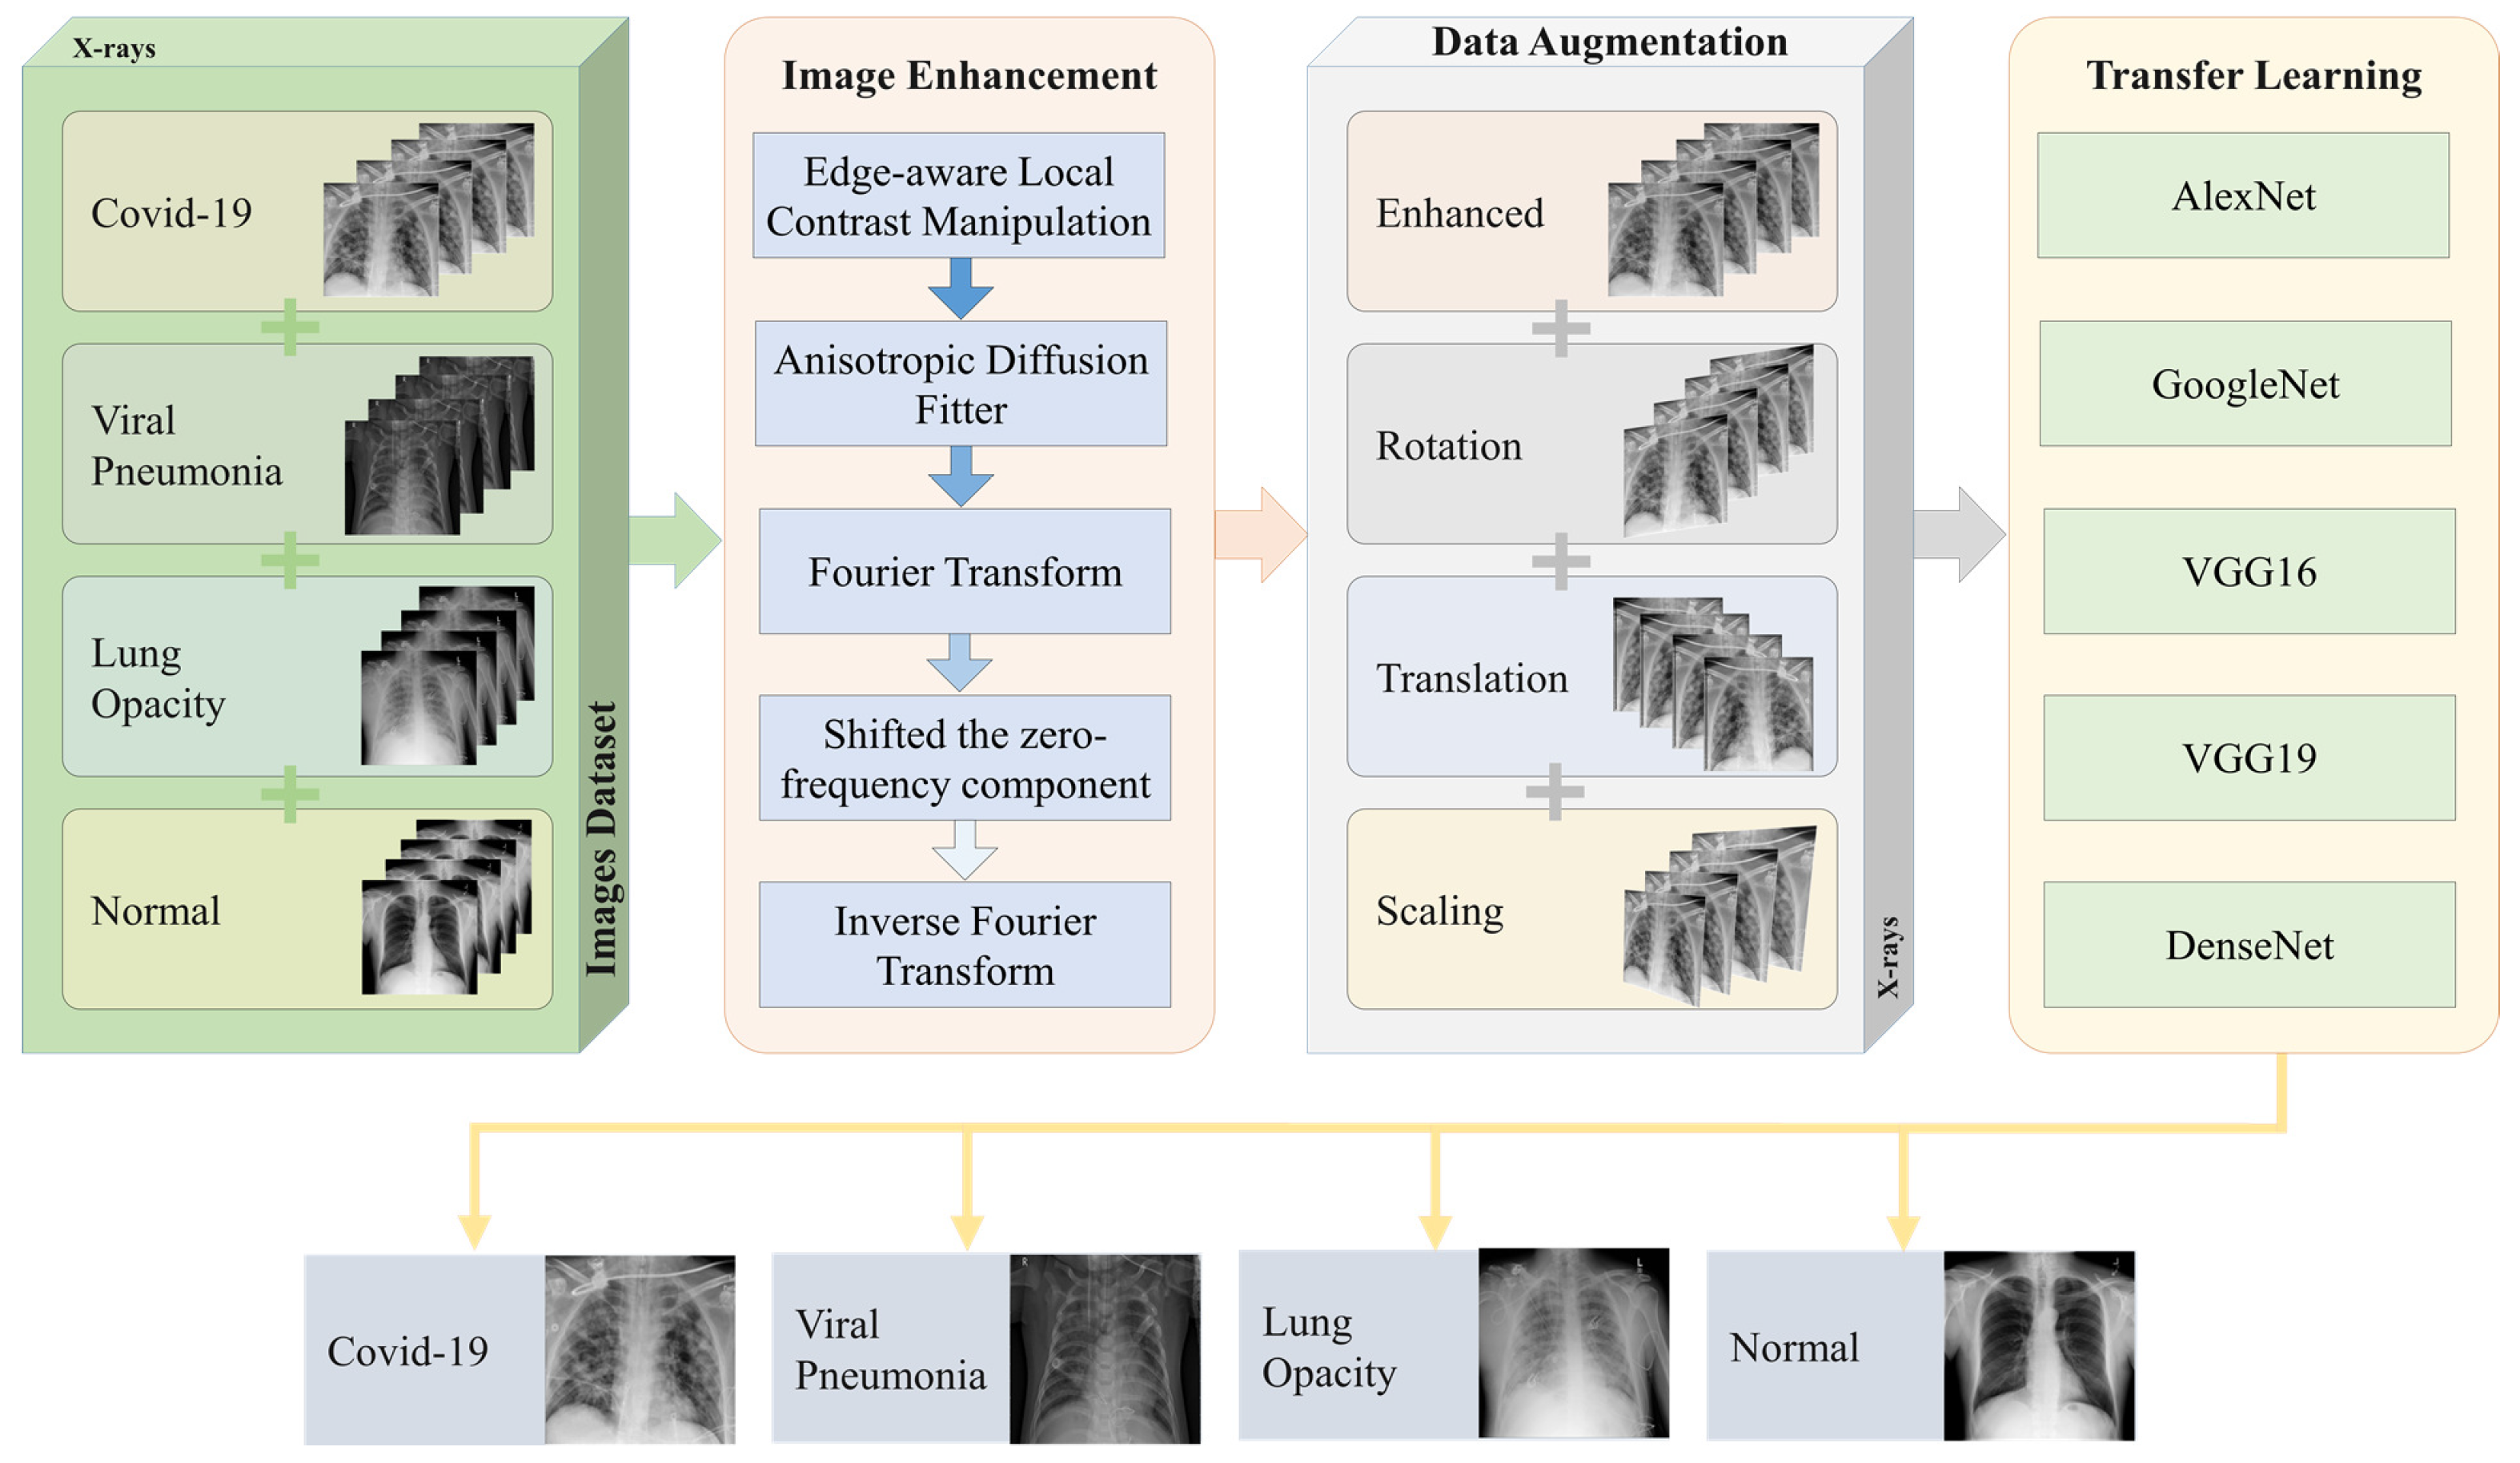

In this paper, we propose an optimized DL technique for the detection of COVID-19 cases using chest X-ray images. The proposed methodology is shown in

Figure 2. A dataset of patients suffering from COVID-19, Viral Pneumonia, Lung Opacity, and those not suffering from any problem (Normal) is used. The image categories of Lung Opacity and Pneumonia are included as part of our study as they have striking similarity with those X-ray images where a person has COVID-19 infection [

31]. Since lung opacity can happen due to various reasons including tuberculosis, cancer, COPD, etc., we included identification, classification, and diagnosis of these diseases under the umbrella of the Lung Opacity category. Now, since the quality of images were not adequate for the training purposes, image enhancement techniques were utilized. The enhancement process is done through several phases, including contrast manipulation, anisotropic diffusion filter, Fourier transform, shifting zero-frequency component, and finally, inverse Fourier transform.

To further increase the number of images in the dataset, data augmentation techniques are applied. These include rotation, translation, and scaling, which together produce a sizable number of synthetically modified images. The original images, along with augmented images for the dataset act as input to various transfer learning algorithms, including modified DL algorithms. These transfer learning algorithms include AlexNet, GoogleNet, VGG16, VGG19 and DenseNet. The transfer learning algorithm, after training, classify the images into four categories, namely, COVID-19, Viral Pneumonia, Lung Opacity, and Normal.

33]. The currently released dataset is made of a total of 21,165 anterior-to-posterior and posterior-to-anterior (AP) chest X-ray images. This dataset was collected from different open access chest X-ray datasets with a challenge to develop a unified COVID-19 infected entities dataset. X-ray Images were categorized into 4 categories as follows: (1) COVID-19 positive instances, (2) Normal instances, (3) Lung Opacity instances, and (4) Viral Pneumonia instances. The lower part of

Figure 2 shows sample images from the studied dataset for each of these 4 categories. The COVID-19 images were collected from padchest dataset, Germany medical school, SIRM, GitHub, Kaggle, and Tweeter; the Normal images were collected from RSNA and Kaggle; Lung Opacity images were collected from the Radiological Society of North America (RSNA) CXR dataset; and the Viral Pneumonia images were collected from the Chest X-ray Images (pneumonia) dataset. The resolution of the various dataset varies in the range of 1112 × 624 to 2170 × 1953 pixels. However, these were preprocessed and scaled down to lower resolution of 299 × 299 pixels in the aggregated released dataset. All images are in the Portable Network Graphics (PNG) format. The frequency of the appearance in terms of number of images of each of the aforementioned categories varies for each of the 4 categories. The Normal category was most represented in the dataset with a count of 10,192 images, which represents ∼48% of the dataset. On the other hand, the count of the COVID-19 images is 3616, which represents ∼17% of the entire dataset. The Lung Opacity image count is 6012 which is equivalent to ∼28% of the entire dataset. The final category (Viral Pneumonia) is the least represented in the dataset, with a total of 1345 images representing ∼6% of the dataset. This category partitioning is depicted in